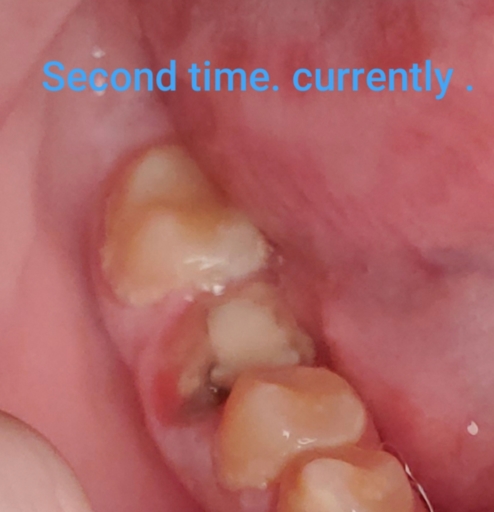

I had tooth that had fillings in it from 3 different places. Back in January this year my gums on the side of that tooth became very inflamed and painful. I went to doctor who treated my cavity that was on the side but my gums wouldn't heal and with time it was going lower and lower also painful. So I went to dentist again (fully convinced I'll need a root canal) doctor took x-ray and said there is no infection so he will place a crown. I wasn't too keen on that idea but I proceed anyway.The tooth was extremely painful once I got that crown on to a point that my dentist wanted to put me on steroids !! Which I was like ...no way thats not happening...anyway after many many painkillers it calmed down the gums are visibly much lower than they were before. The problems is I can't bite on that tooth at all...I have pain every time some food gets there ...i have been walking with this since January with a crown that i paid $1300 and can't even use it ...I am in a really bad financial situation so I was convinced since I had it done that most likely I need that root canal anyway. So I just out put up with it...Recently I went to different doctor to just do cleaning and asked him if he can x-ray that tooth to see If I have an infection and he said it doesn't. He even let me keep a picture for proof. Why does it hurt if its not infected ? Does that mean that I just need bite adjustment ? I'm sacred to come back to the doctor who did that crown because I feel like he's going to try to convince me to get root canal...and I don't have the money for that...what should I do ?